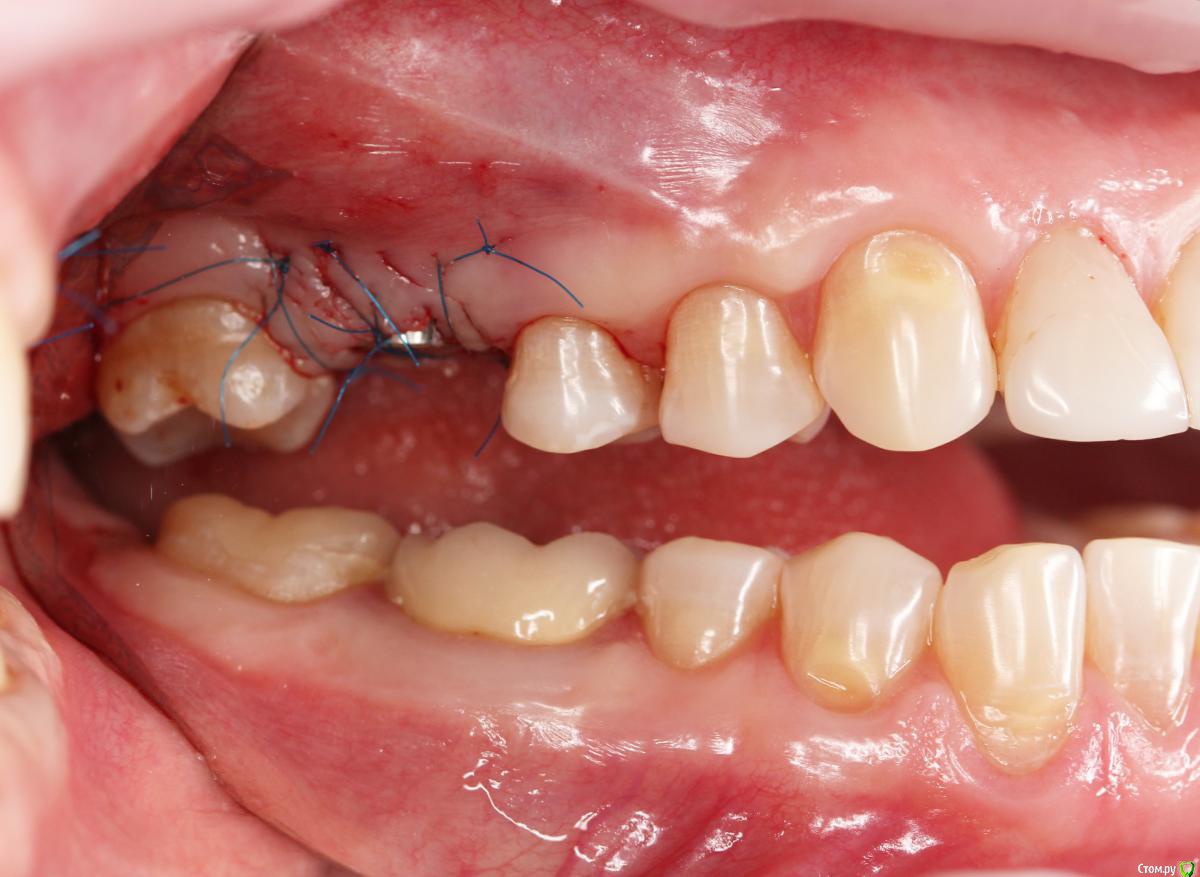

Dmitry DK Опубликовано 10 сентября, 2019 Поделиться Опубликовано 10 сентября, 2019 Фотопротокол к сожалению не полный, но ничего особенного и не проводилось. 1) Открытый синус, удален пломбировочный материал из пазухи, уложен 1 г Bio-oss 2) через 6 мес имплантация Straumann SP 4.1\10 Результат через год 9 Ссылка на комментарий